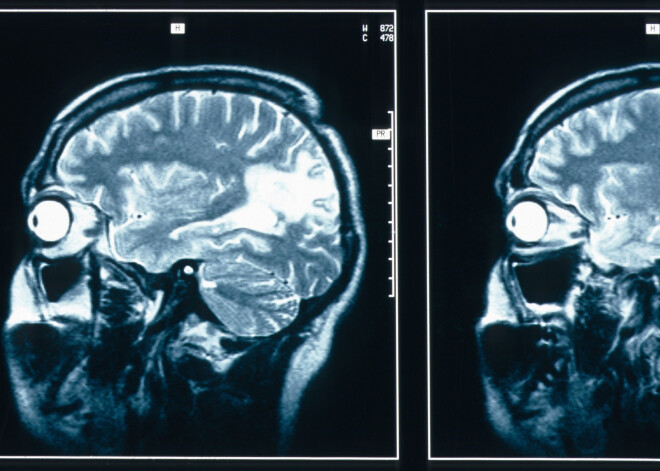

Turpmākās dienas bija murgpilnākās Džordžijas dzīvē – tika veiktas neskaitāmas skenēšanas un biopsijas, kā rezultātā atklājās – vēža šūnas radījušas 4 centimetru lielu caurumu viņas galvaskausā.

Kopš diagnozes dienas Džordžija pārcietusi vairākas operācijas, kuru laikā ķirurgi ar ģipsi aizpildījuši caurumu galvaskausā, bet vietā, kur uz sejas bija uzmetusies “pinne”, sievietei uzliktas 23 iespaidīga izmēra šuves.